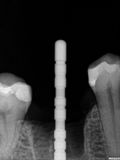

fredlibc | all galleries >> Galleries >> NSankhyan - immedaite 46 > R1.jpg

R1.jpg